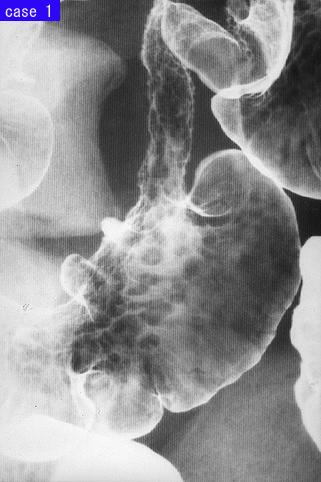

疾病(病理主体)的分类转移性肿瘤/

部位(按器官分)大肠/横结肠

检查方法X线

肿瘤最大直径40以上